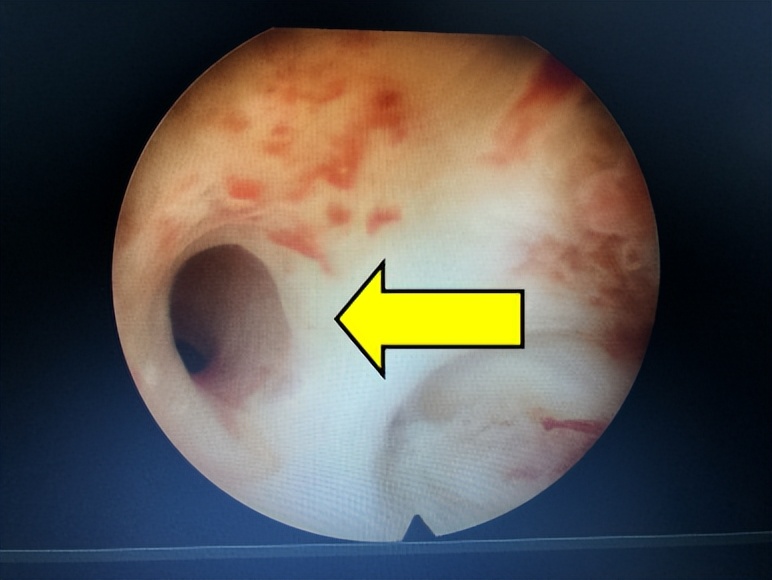

△宫腔镜下正常宫腔形态